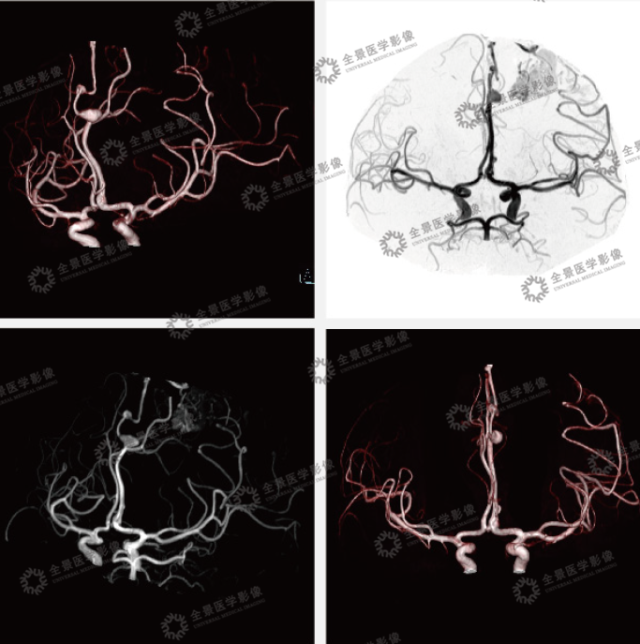

案例:中老年男性,头痛 2 周,既往有脑出血病史。颅脑 MRA 示:左侧大脑中动脉及大脑前动脉远段增粗,左侧额叶见畸形的血管团,由左侧大脑中动脉分支参与供血,左侧大脑前动脉分支可疑参与供血。

左侧大脑前动脉拼周支分别见梭形扩张及浆果样的动脉瘤,最大直径分别为 13 mm、5 mm, 前者呈窄基底与载瘤动脉相连,瘤颈约 1 mm, 后者呈宽基底与载瘤动脉相连。左侧大脑前动脉拼周支两枚动脉瘤。

结论:左侧额叶动静脉畸形 (AVM), 左侧大脑前动脉动脉瘤。